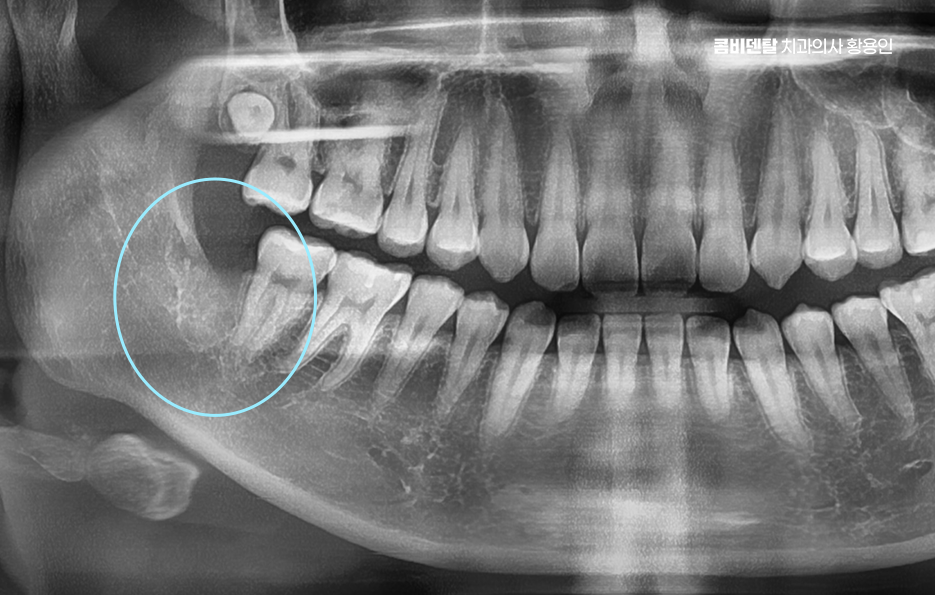

명동치과 그런데 문제는 이 두 부위에 생긴 충치나 손상이 단순히 그 치아만의 문제가 아니라, 주변 치아 등에도 영향을 줄 수 있다는 점에서 원인을 제대로 알고, 그에 맞는 해결 방법을 빠르게 선택하는 게 중요한데 먼저 사랑니는 맨 뒤쪽에 위치한 제 3 대구치로 대부분 10대 후반에서 20대 초반 사이에 맹출하기 시작하며 공간이 부족하거나 방향이 비정상적인 경우가 많아서 완전히 나오지 못하고 잇몸이나 턱뼈 안에 매복되는 경우도 많이 있어요

명동치과 게다가 사랑니의 위치가 문제인데 맨 뒤에 있기 때문에 일반 칫솔로 닦기 어렵고 양치 습관이 조금만 어긋나도 치석과 세균이 금세 쌓이게 되며 이때 사랑니에만 문제가 생기면 그나마 다행이지만 대부분은 사랑니 바로 앞에 있는 두 번째 큰 어금니까지 충치나 염증이 번지게 될 수 있었어요

그래서 사랑니 하나 때문에 멀쩡했던 어금니를 잃거나 수명이 급격히 저하되는 일이 의외로 자주 발생하는 케이스이며 사랑니 충치보다 더 무서운 건 이웃 어금니 손상이라는 말이 괜히 나오는 게 아닌 거예요

사랑니가 맹출하는 방향도 문제인데 수평으로 누워 있거나, 비스듬히 자라는 경우가 많다보니 이렇게 되면 앞쪽 어금니에 대한 압박을 계속 주다 보면 뿌리 쪽에 흡수가 생기거나, 치아 사이에 깊은 충치가 생기기도 해서 겉으로는 안 보이는데 내부에서부터 썩어 들어가는 경우가 많기 때문에, 이미 증상이 생겼을 때는 치료가 늦는 경우도 많이 있었어요

명동치과 그렇다면 해결 방법에 대해 알아보면 사랑니는 불필요한 경우 발치가 좋은 해결책이며 특히 부분적으로만 나와 있고, 충치가 있거나 앞 어금니에 영향을 주고 있다면 주저하지 말고 발치 계획을 세우는 게 중요하며 사랑니를 남겨두면 치료 비용과 시간이 더 드는 결과로 이어지는 경우가 많고 결국은 더 건강한 어금니까지 잃게 되는 상황이 생길 수 있었어요.